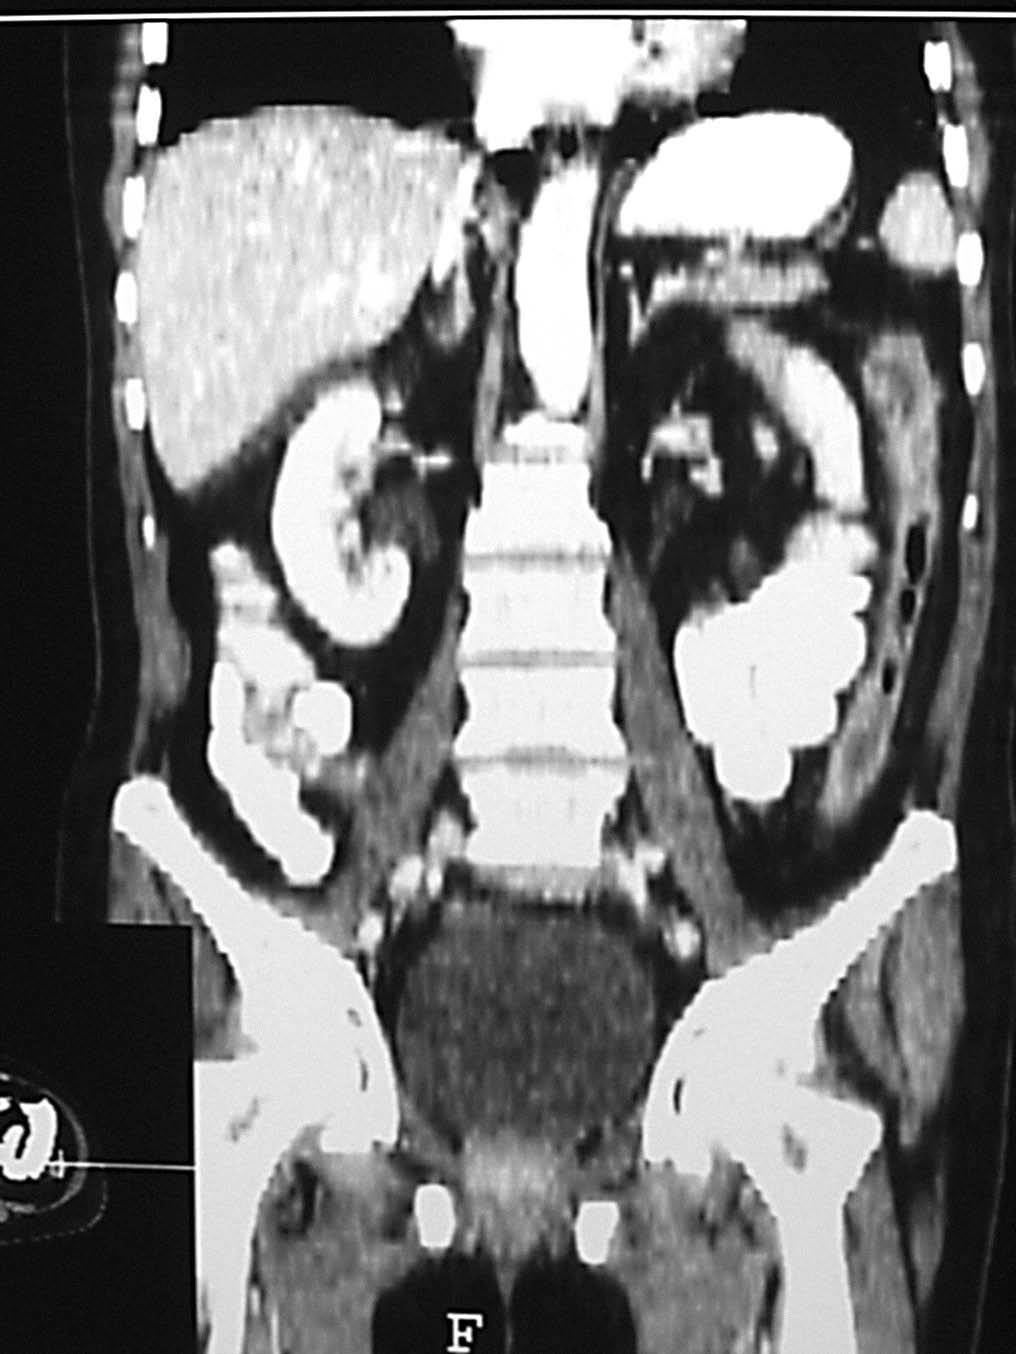

Desde el punto de vista tomodensitométrico (fig. 12) y de la RM los criterios semiológicos son más o menos similares: el engrosamiento mural y la hiperemia característica de una situación inflamatoria activa. Se describe el hecho de que el engrosamiento mural del colon suele ser más marcado en la colitis granulomatosa que en la ulcerosa, lo mismo que la irregularidad de los contornos, que suele ser también más acentuada en los casos de colitis granulomatosa.

Fig. 12.--Enfermedad de Crohn. A) La tomografía computarizada (TC) muestra la afectación del colon de carácter segmentario.(B) En la reconstrucción en plano coronal (MPR) puede apreciarse el marcado engrosamiento mural del colon descendente.